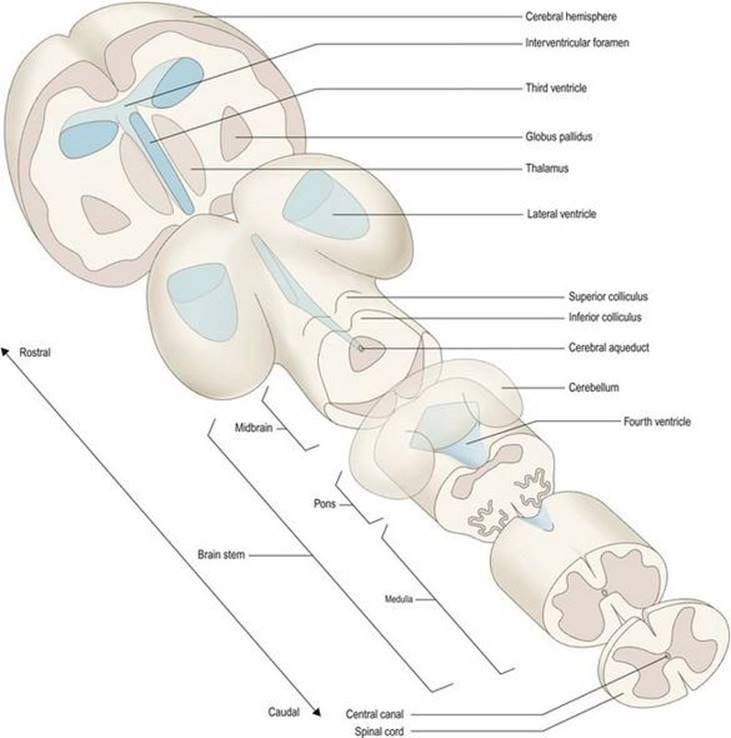

برخی از نامهای زیربخشهای جنینشناسی مغز معمولاً برای اهداف توصیفی استفاده میشوند و بنابراین، دانستن قسمتهایی از مغز بالغ که متعاقباً در آن رشد میکنند مفید است (جدول ۱.۱). از میان سه بخش اصلی مغز، پیش مغزی یا پیش مغزی به مراتب بزرگترین است. به آن مغز نیز میگویند. در داخل مخ، تلانسفالن بیشترین رشد بیشتری را تجربه میکند و باعث ایجاد دو نیمکره مغزی میشود. اینها از یک لایه بیرونی ماده خاکستری (قشر مخ) و یک توده درونی ماده سفید تشکیل شده اند که در داخل آن گروههای مختلفی از هستهها مدفون شده اند (بزرگترین آنها جسم مخطط است ). دیانسفالون عمدتاً از تالاموس که شامل گروههای سلولی متعددی است و ارتباط نزدیکی با قشر مغز دارد. مزانسفالون یا مغز میانی نسبتاً تمایز نیافته است (هنوز یک حفره لوله مانند مرکزی که توسط ماده خاکستری احاطه شده است را حفظ میکند). متانسفالون به سمت پونز و مخچه پوشاننده رشد میکند، در حالی که میلنسفالون بصل النخاع (بصل النخاع) را تشکیل میدهد. مدولا، پونز و مغز میانی در مجموع به عنوان ساقه مغز شناخته میشوند (شکل ۱.۱۰).

شکل ۱۰-۱ نمایش شماتیک زیربخشهای اصلی و نشانههای مغز.

شکل ۱۰-۱ نمایش شماتیک زیربخشهای اصلی و نشانههای مغز.

همانطور که مغز رشد میکند، حفره مرکزی آن نیز دستخوش تغییرات قابل توجهی در اندازه و شکل میشود و سیستمیاز حفرهها یا بطنها را تشکیل میدهد (شکل ۱.۱۰ و شکل ۱.۱۸ را ببینید) که حاوی مایع مغزی نخاعی (CSF) است.

شباهتهایی بین رشد جنینی مغز و تغییرات عمده ای که مغز در طی صعود به مقیاس فیلوژنتیک یا تکاملی از حیوانات ساده به پیچیده تر متحمل شده است ترسیم شده است. در حالی که این مطمئناً یک سادهسازی بیش از حد است، این مفهوم دارای شایستگی معرفی برخی از بخشهای اصلی مغز، و روابط آنها با یکدیگر، به شیوهای گرافیکی و به یاد ماندنی است (شکل ۱.۱۰).

سیستم بطنی

طرح بسیار ساده شده مغز پایه، که در بالا توضیح داده شد، طرح مفیدی است که در آن میتوان وضعیت کلی سیستم بطنی را در نظر گرفت (شکلهای ۱.۱۰، ۱.۱۲، ۱.۱۸). همانطور که کانال مرکزی نخاع به سمت ساقه مغز بالا میرود، به تدریج در جهت پشتی حرکت میکند و در نهایت باز میشود تا یک فرورفتگی کم عمق و لوزی شکل در سطح پشتی مدولا و پونز (قسمت مغزی عقبی ساقه مغز) ایجاد شود.) زیر مخچه. این بطن چهارم است.

شکل ۱.۱۸ سیستم بطنی مغزی.

شکل ۱.۱۸ سیستم بطنی مغزی.

در مرز منقاری حوضچهها، دیوارههای بطن چهارم به هم میرسند و بار دیگر یک لوله باریک به نام قنات مغزی را تشکیل میدهند. قنات مغزی به درون ماده ای از ساقه مغز که در طول مغز میانی در زیر کولیکولهای تحتانی و فوقانی قرار دارد فرو میرود. در محل اتصال مغز میانی و جلوی مغز، قنات به بطن سوم باز میشود، محفظهای شکافمانند، باریک از پهلو به پهلو، اما در ابعاد پشتی و شکمیو روسترو دمیگسترده است. دیوارههای جانبی بطن سوم توسط تالاموس و هیپوتالاموس دیانسفالون تشکیل شده است. در نزدیکی انتهای منقاری بطن سوم، یک روزنه کوچک، سوراخ بین بطنی (فورامن مونرو)، با یک محفظه وسیع، بطن جانبی ارتباط برقرار میکند.، در هر نیمکره مغزی. سیستم بطنی حاوی CSF است که توسط شبکه کوروئید ترشح میشود.

ساقه مغز

هنگامیکه مغز به صورت خارجی مشاهده میشود، نیمکرههای بزرگ مغز بسیاری از ساختارهای دیگر را مبهم میکند، اما یک بخش ساژیتال وسط (شکل ۱.11B، ۱.12A) بیشتر ویژگیهای اصلی مغز اصلی را نشان میدهد. ساقه مغز را میتوان به وضوح در هر دو بخش ساژیتال وسط و نمای شکمی(شکل ۱.۱۱، ۱.۱۲) مغز مشاهده کرد. ساقه مغز از بصل النخاع، پونز و مغز میانی تشکیل شده است.

ساقه مغز تنها بخش کوچکی از کل مغز را تشکیل میدهد، اما بسیار مهم است. از طریق آن، مسیرهای فیبر عصبی صعودی و نزولی که مغز و نخاع را به هم پیوند میدهند، میگذرد (شکل ۱.۱۹). اینها اطلاعات حسی را از تنه و اندامها حمل میکنند و به آنها اجازه حرکت میدهند. ساقه مغز همچنین شامل محلهای منشأ و پایان بسیاری از اعصاب جمجمه ای است که مغز از طریق آنها سر را عصب میکند. علاوه بر این، در داخل ساقه مغز مراکزی قرار دارند که عملکردهای حیاتی مانند تنفس، سیستم قلبی عروقی و سطح هوشیاری را کنترل میکنند.

مغز میانی نسبتاً کوچکی در منقاری بر روی پونز قرار دارد. در سطح پشتی آن میتوان برجستگیهای گرد کولیکولهای فوقانی و تحتانی را مشاهده کرد که در زیر آنها قنات مغزی قرار دارد (شکلهای ۱.۱۰ – ۱.۱۲).

دیانسفالون و نیمکرههای مغزی

مغز به طور معمول به مغز عقبی، مغز میانی و پیش مغزی تقسیم میشود.

مغز عقبی بیشتر به بصل النخاع، پونز و مخچه تقسیم میشود.

مدولا، پونز و مغز میانی ساقه مغز را تشکیل میدهند.

پیش مغز از دیانسفالون (تالاموس و هیپوتالاموس) و نیمکره مغز تشکیل شده است.